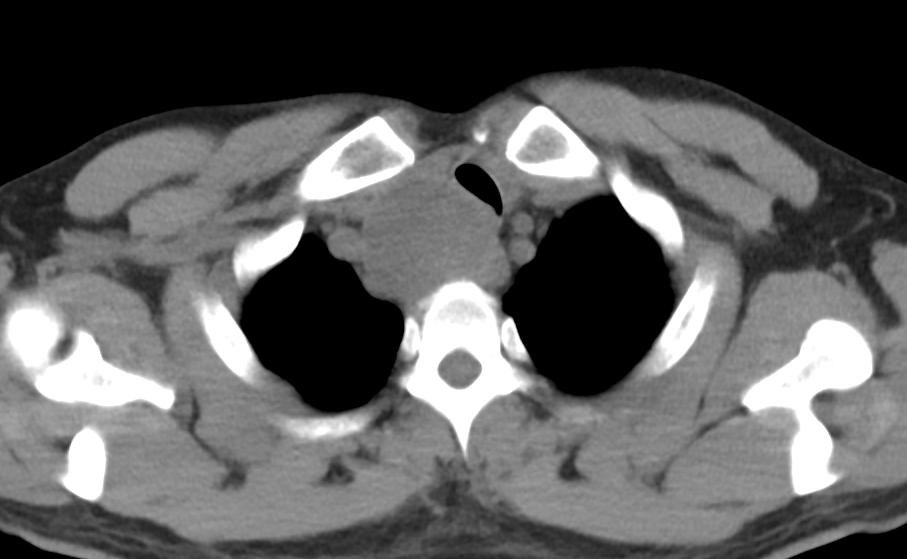

7月12日,明先生来到嘉定区中心医院就诊,超声结果显示,甲状腺左叶可见一直径7cm的结节,并且向胸骨后方延伸。CT结果显示上纵膈占位,气管局部受压移位变形,局部管腔变窄。喉镜结果显示右侧声带麻痹。结合病史及影像资料,考虑甲状腺结节压迫喉返神经导致声音嘶哑。